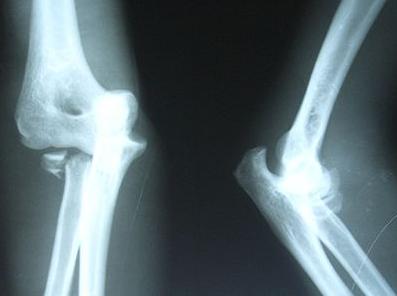

骨不连是属于骨折后的并发症,骨折端位不好,受到药物的刺激,过度的牵引,严重开放性骨折,软组织损伤较大,血管受损伤挤压造成患部血运不良,骨组织感染,内固定材料过敏等,只要达到一定的时间强度的刺激,都会产生一系列的神经、内分泌、免疫功能的改变而引发骨不连。

骨不连只是骨髓炎发生时的一种情况,但是不是同一种疾病,骨不连在治疗不及时会转变成骨髓炎,这时需要引起人们的重视的。再骨折手术治疗的过程中,如果出现延迟愈合或是骨不连时,就要好好研究一下真正的病因所在。

这里不得不提的是手术因素,因手术本身就具有创伤性,会造成骨折周围软组织破坏,由于本身的抵抗力下降,加上手术过程中不注意防止细菌性感染,造成骨折端易受感染的因素更大,如果正好是由于细菌引起的骨不连,就会出现骨髓炎跟骨不连同时发生,如果不是由于细菌感染引起的骨不连,而是术后呈现骨不连的情况,由于时间长,周围组织形不成很好的防御功能,在治疗上不及时而转变成慢性骨髓炎。